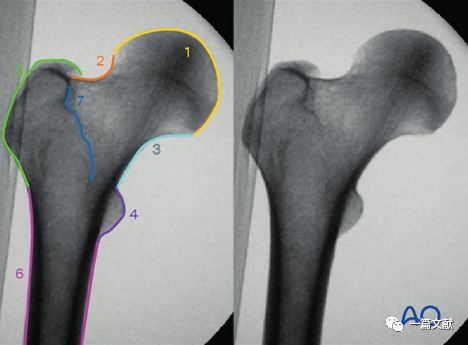

正位片图像解剖标记识别1,股骨头;2,股骨颈;3,内侧缘;4,小转子;5,大转子;6,股骨干;7,转子间线。

正位片的作用:判断内外翻畸形、旋转畸形、侧方移位畸形。

左侧正位片显示颈干角,右侧侧位片显示前倾角。

下图左侧正位片与右侧的轴位片,显示了内固定的良好位置(位于头颈中心与髓腔中心)。需要注意的是这些标准的术中透视图像,只有在良好骨折复位的基础上才能获得。

只有如下图右侧的轴位片图像才能判断内固定在头颈骨块中的位置(左侧为侧位片)